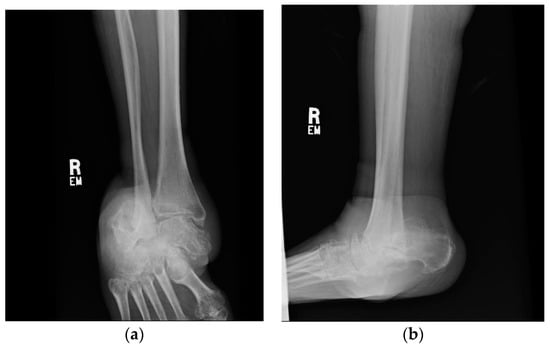

1.1. Case Presentation (Clinical Summary)

1.1.1. Initial Presentation

1.1.4. Post-Operative Imaging